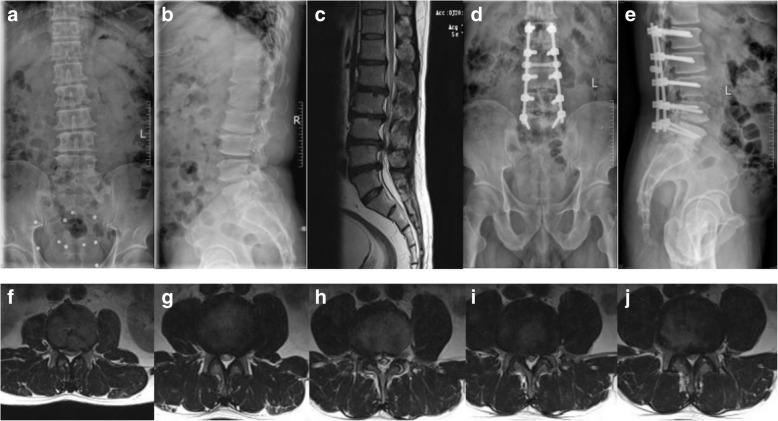

A retrospective study was performed on the clinical data of 71 patients with degenerative lumbar stenosis who underwent multi-level (at least 3 levels) posterior lumbar spinal fusion from January 2013 to December 2016. Two groups were divided according to lamina and posterior ligamentous complex (PLC) maintenance of proximal fixed vertebrae in surgery. In the 22 patients of group A, the proximal fixed vertebral lamina and PLC were not resected, and in the 49 patients of group B, the proximal fixed vertebral lamina and PLC were resected completely. Age, sex, body mass index (BMI), number of fixed vertebrae and fused levels, spinopelvic parameters, coronal Cobb angle, and modified Pfirrmann grading system were measured for each patient. A Cox proportional hazards model was used to analyze risk factors for upper ASD.

No symptomatic ASD was found during the follow-up period. Patients who underwent proximal fixed vertebral lamina and PLC resection had a significantly higher percentage of radiographic ASD (P = 0.042). The Cox proportional hazards model showed that age, sex, BMI, preoperative lumbar lordosis, sacral slope, pelvic tilt, coronal Cobb angle, number of fixed vertebrae, and interbody fusion levels had no significant differences for radiographic ASD. But a preoperative modified Pfirrmann grade higher than 3, a high degree of preoperative pelvic incidence, and more decompressed levels had statistical significance (P = 0.024, 0.041, and 0.008, respectively).

A preoperative modified Pfirrmann grade higher than 3, a high degree of preoperative pelvic incidence, and more decompressed levels might be risk factors for upper radiographic ASD after multi-level posterior lumbar spinal fusion surgery.